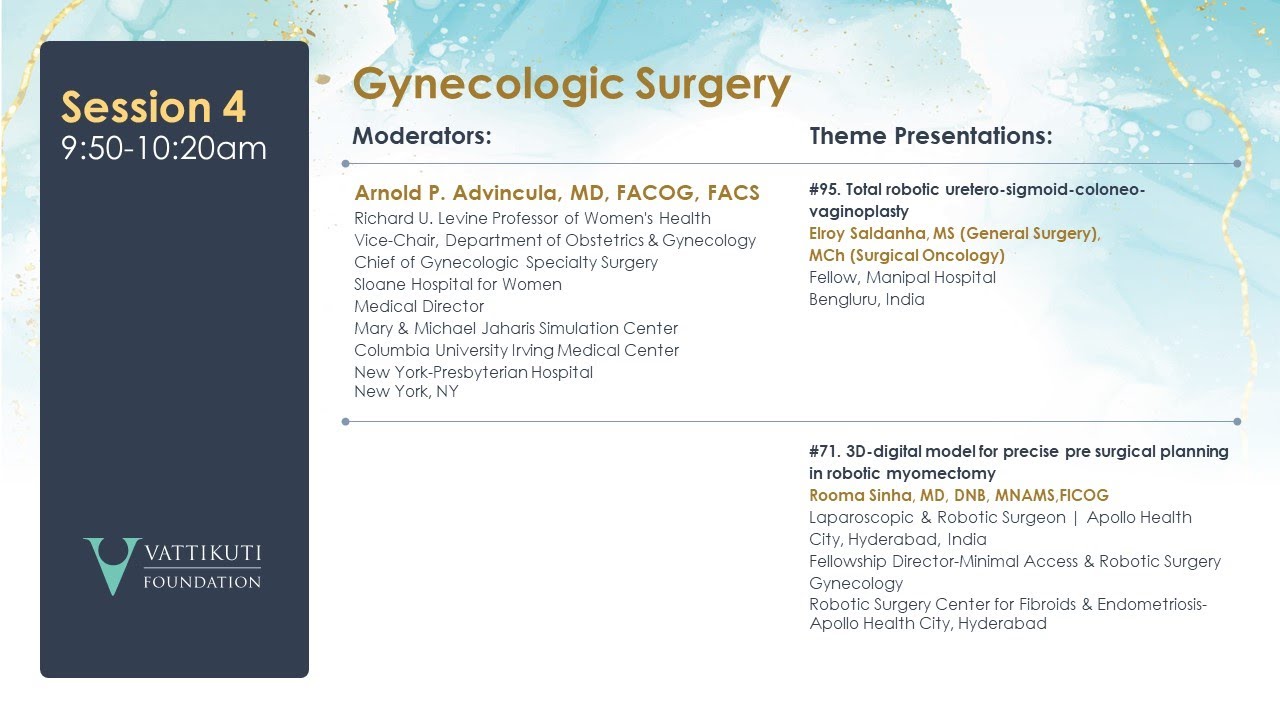

Session 4: Gynecologic Surgery, Humans on the Cutting Edge of Robotic Surgery

3D print model for precise pre surgical planning in Robotic Myomectomy